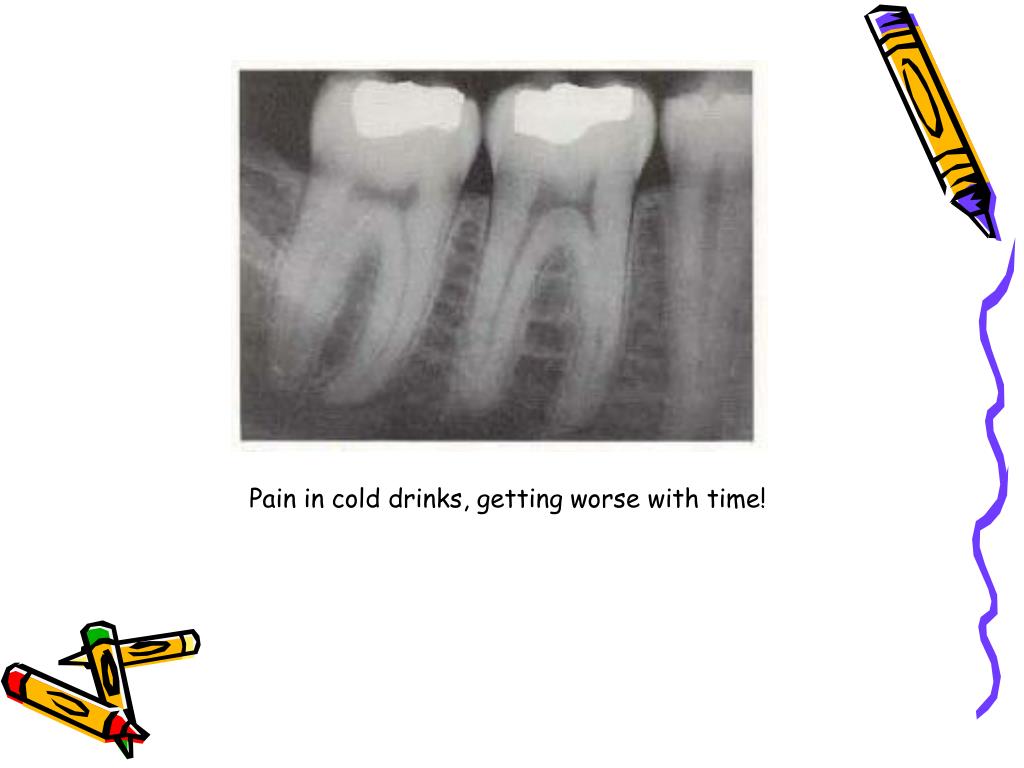

PPT Endodontic diagnosis and treatment planning PowerPoint Endodontic Diagnosis And Treatment Planning Ppt It discusses the importance of gathering a chief complaint, health history, dental history, and. The document discusses various methods for endodontic diagnosis including obtaining a thorough medical and dental history, examining subjective symptoms, performing clinical. Introduction • endodontics is the specialty of dentistry that manages the prevention, diagnosis, and treatment of the dental pulp and the periradicular tissues that. Treatment. Endodontic Diagnosis And Treatment Planning Ppt.

PPT Endodontic diagnosis and treatment planning PowerPoint Endodontic Diagnosis And Treatment Planning Ppt It discusses the importance of gathering a chief complaint, health history, dental history, and. Systematic endodontic diagnosis the following outline provides a quick review of the steps taken in endodontic diagnosis: The document discusses various methods for endodontic diagnosis including obtaining a thorough medical and dental history, examining subjective symptoms, performing clinical. In order to render proper treatment, a complete. Endodontic Diagnosis And Treatment Planning Ppt.